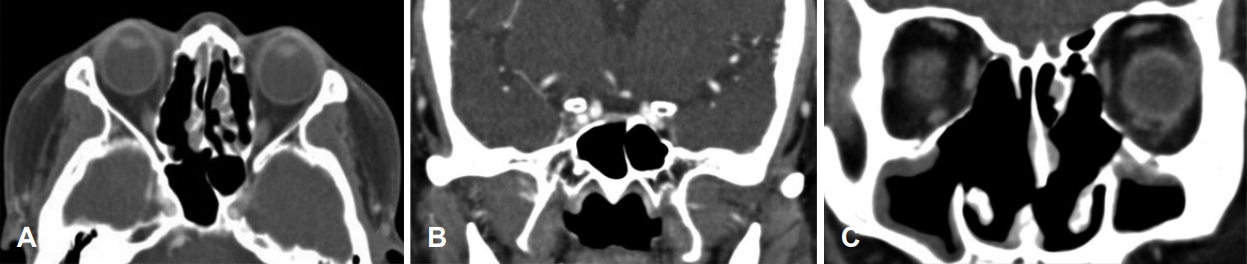

58세 여자 환자가 내원 2일 전부터 시작된 두통과 가벼운 비회전성 어지럼증으로 본원 신경과에 내원하였다. 환자는 기저 질환이 없이 건강하던 자로 두통은 간헐적으로 머리 전반적인 부위에서 발생한다고 하였고, 신경학적 검사상 이상소견은 보이지 않았다. 말초성 현훈 감별 위해 두부충동 검사, 두위충동 검사, 두위안진, 냉온교대 온도안진 검사(bithermal caloric test) 등을 시행하였으나 특이 소견은 관찰되지 않았다. 이에 추가 정밀 검사 및 보존적 치료를 위해 신경과로 입원하였다. 일반 혈액 검사에서 백혈구는 10.07×103/uL에 중성구 81%, 적혈구 침강속도는 86 mm/hour로 증가되었으나 그 외 검사상 다른 이상 소견은 보이지 않았다. 뇌 확산 자기공명영상(brain MR diffusion)을 촬영하였고, 허혈성 병변 및 뇌실질의 병변은 확인되지 않았으나, 우측 사골동과 접형동 부비동염 의심 소견이 확인되었다. 입원 2일째 환자가 갑작스러운 복시와 우측 안검하수를 호소하여 시행한 안과 검진상 시력, 안압 등은 정상이었고, 안구 운동 시 우안의 내전, 외전, 상전, 하전 제한과 안검하수가 관찰되었다(Fig. 1). 우측 사골동과 접형동 부비동염 및 우측 동안 및 외전 신경 마비 의심하에 부비동 전산화단층촬영(paranasal sinus CT, PNS CT) 및 후두와 자기공명영상(posterior fossa MRI)을 시행하였다. MRI에서 팽윤된 양측 해면정맥동과 주변 경막의 비후 소견이 관찰되었으며, 상기 소견은 우측이 더 심하였고 혈전 형성은 보이지 않았다(Fig. 2). PNS CT상 우측 전두동, 상악동, 사골동과 접형동의 연부조직음영이 있었으며, 좌측 상악동, 사골동과 접형동에도 일부 음영증가 소견이 보였고, 골결손은 보이지 않았다(Fig. 3). 환자는 코막힘, 후각 감퇴, 콧물, 재채기 등의 비증상은 호소하지 않았으나, 비강 검사상 좌측 비중격 만곡증 및 양측 비용 소견이 관찰되었다. 임상학적 양상과 영상 소견을 종합한 결과 급성 부비동염에 병발된 해면정맥동혈전염으로 인한 우측 동안 및 외전 신경마비로 의심되어 부비동 내시경 수술과 항생제와 스테로이드 정맥주사(ampicillin/sulbactam 1.5 g tid, cefotaxime 1 g tid, metronidazole 500 mg tid, dexamethasone 5 mg bid)를 진행할 것을 계획하였다. 입원 3일째, 전과 후 비중격 교정술과 양측 부비동 내시경술을 시행하였다. 전신마취하에 비중격 교정술 후 우측 전두동, 상악동, 사골동의 비용과 병변 점막을 제거하면서 자연공을 충분히 넓혔으며, 접형동 개구술을 통해 배농을 시행하였다(Fig. 4). 좌측 사골동, 상악동, 접형동도 비용과 병변 점막 제거 및 개방술을 진행하였다. 술 후 1일째, 두통, 어지럼증과 안검하수는 호전되었으나, 복시는 지속되는 양상이었다. 술 후 5일째에 안검하수 증상은 개선되었고, 우측 주시시 여전히 복시를 호소하였다. 술 후 7일째 퇴원하고 경구 항생제, 경구 스테로이드, 비강 스테로이드제(amoxicillin/clavulanate potassium 1 g bid, prednisolone 10 mg bid, fluticasone 5 mg qd)를 3주간 사용하였다. 추적 관찰하기 위해 촬영한 PNS CT상 양측 상악동, 사골동과 접형동의 부비동염 양상은 대부분 호전되었다(Fig. 5). 술 후 1개월째 안과 진료를 통해 복시가 개선된 것으로 확인되었고, 수술 2개월경 시행한 안과 검진상에서 외안근 기능이 모두 정상화된 것을 확인할 수 있었다(Fig. 6).

해면정맥동 혈전염의 진단을 위해서는 전산화단층촬영이 가장 중요하며 우선적으로 시행되어야 한다. 이를 통해 접형동의 함기화 정도 및 골미란 여부와 접형동 병변과의 관계성을 확인해 볼 수 있으며, 골미란 소견이 있거나, 시력 저하, 복시, 안검하수 등 뇌신경마비 소견이 보이는 경우 뇌 자기공명영상을 추가로 시행해야 한다[8,9]. 해면정맥동 혈전염의 자기공명영상 소견으로는 해면정맥동의 비대칭적 팽창과 혈전 형성을 시사하는 해면정맥동 내 불규칙한 다발성 충만 결손(filling defect), 해면정맥동 내 내경동맥(intracavernous internal carotid artery)의 현저한 내경 감소 및 해면정맥동 주위 경막의 조영증강 등이 있고, 상안정맥 확장이나 안구 돌출 양상도 보일 수도 있다[5,7,10]. 본 증례에서는 뇌 자기공명영상에서 양측 해면정맥동의 팽창 및 주변 경막의 조영 증강 소견을 보여 해면정맥동 병변을 의심해볼 수 있었으며, 충만 결손은 확인되지 않아 혈전은 뚜렷하게 생성되지 않았음을 확인하였다. 영상 소견에서는 양측 해면정맥동 혈전염이 확인되었지만, 환자는 우측에서만 안증상을 보였다. 해면정맥동 혈전염은 양측으로 교통되어 있어서, 원인 질환이 일측이라도 양측으로 금방 전파될 수 있다[7,11]. 본 증례에서는 우측 사골동염과 접형동염이 상대적으로 심하였기 때문에 안증상이 우측에서 먼저 확인되었고, 빠른 치료가 없었으면 좌측 안증상도 발생했을 가능성이 있다고 생각된다.